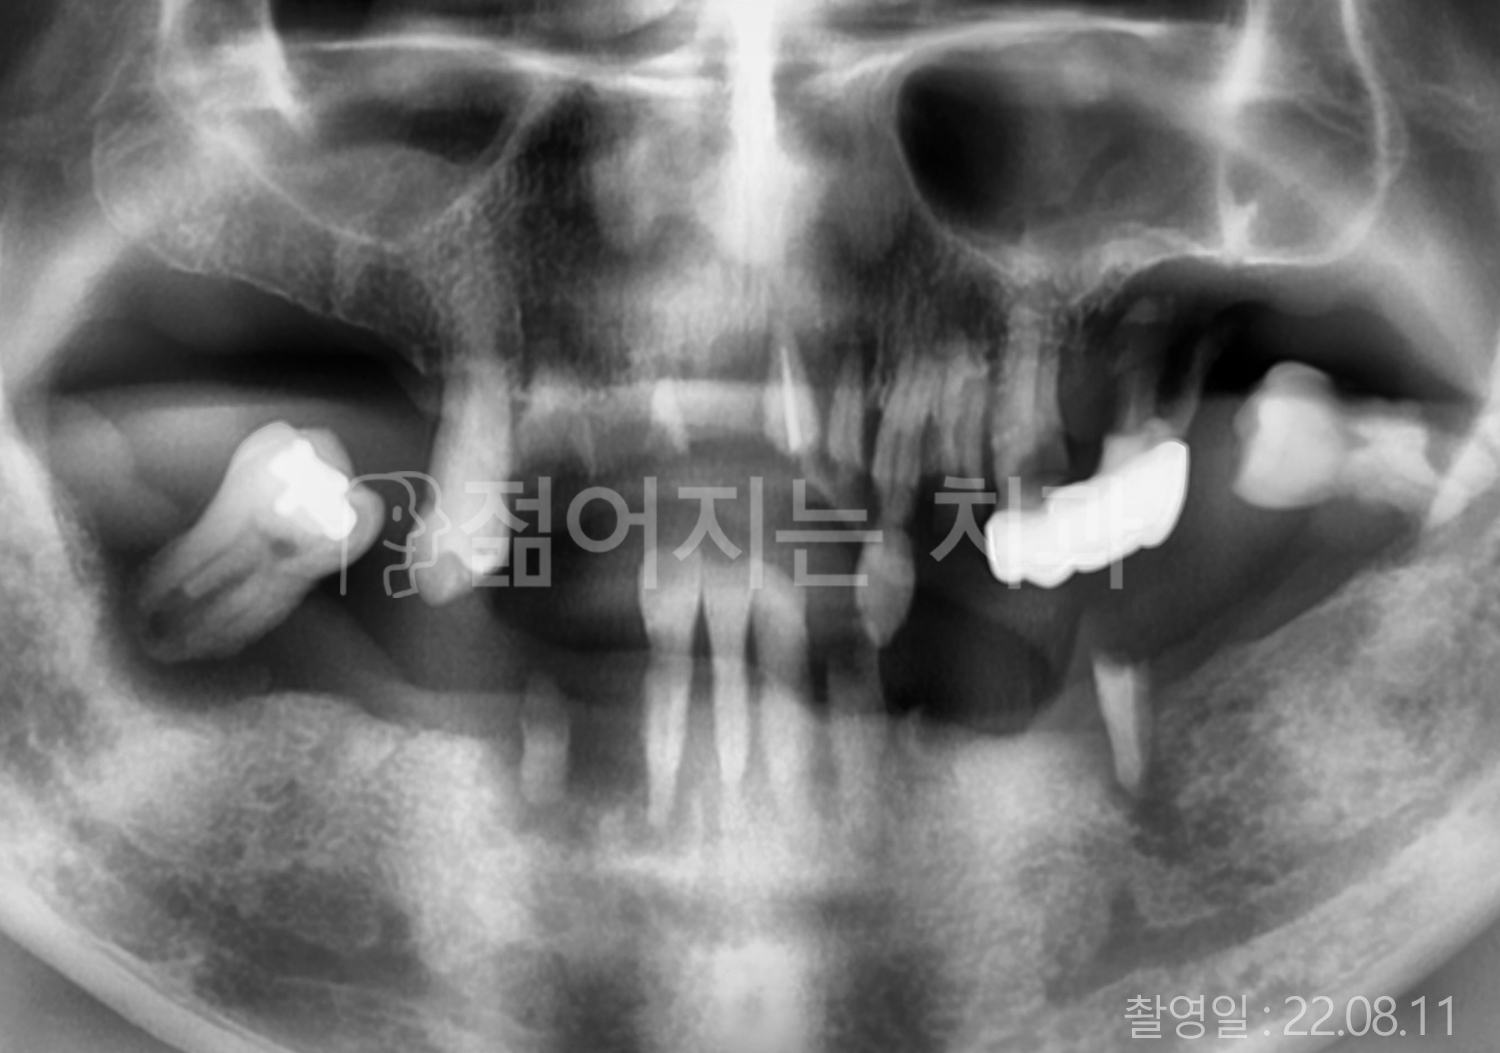

60대 고혈압, 고지혈증

전체치아 10개 이상 임플란트

60대 고혈압

70대 고혈압